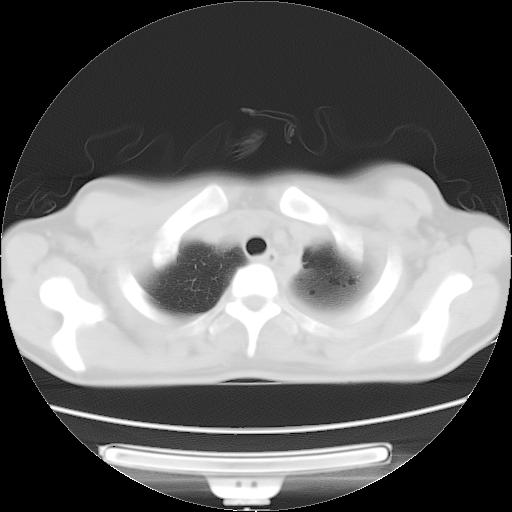

标题: CT21561:外院胸片提示胸腔积液,行CT检查。 [打印本页]

女,29岁,胸部不适,在外院胸片提示胸腔积液,到我院ct检查。

肺窗: